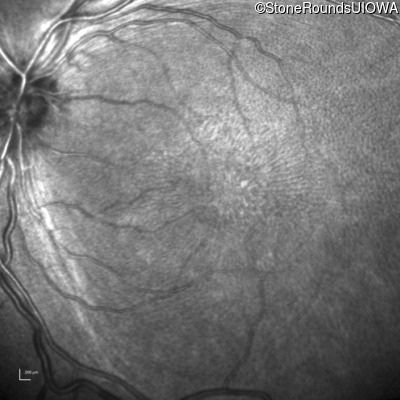

Infrared Fundus Photograph - Right - 10/40

Exemplar